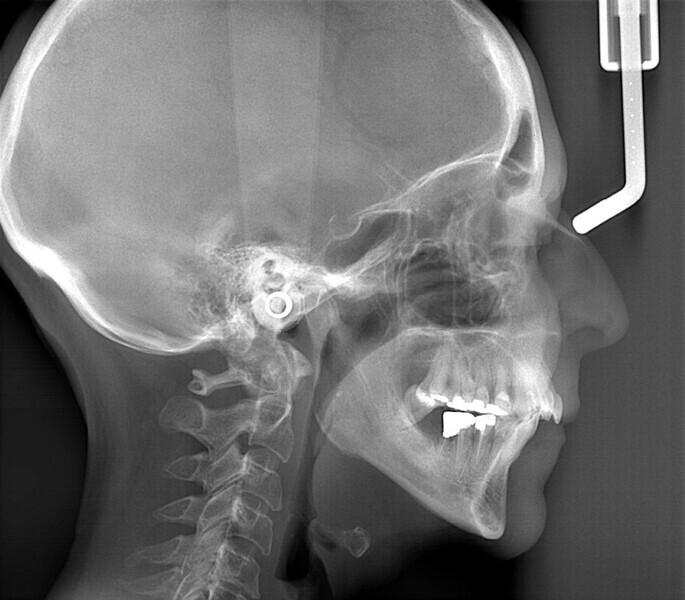

The periodontal treatment of an adult patient undergoing treatment with aligners is illustrated in demonstration of these points. Orthodontic planning considered the extra-oral photographs (Fig. 1) and intra-oral photographs (Figs. 2 & 3). Intra-oral scanning (Fig. 4) and radiographic documentation using panoramic radiographs and cephalometric radiographs (Figs. 5 & 6) were also carried out. From a periodontal perspective, periapical radiographs were recommended (Fig. 7), as this was an adult patient who smoked and showed clinical signs of advanced periodontal disease. Prior periodontal treatment was carried out (Fig. 8) to begin treatment with aligners (Fig. 9).